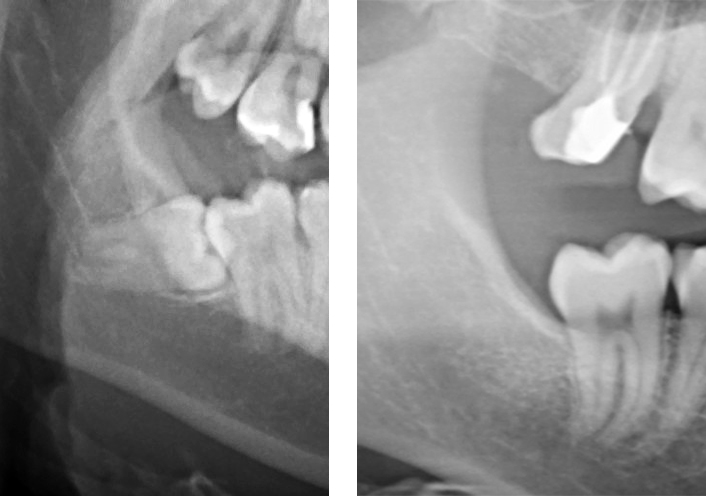

Chirurgia degli ottavi inclusi

L’estrazione del “dente del giudizio” in inclusione ossea è un vero e proprio atto chirurgico impegnativo sia per il paziente che per l’operatore, che spesso costringe l’odontoiatra non adeguatamente formato ad inviare il paziente a colleghi più competenti. La nostra abilità nella chirurgia orale ci permette di eseguire in studio questi interventi nella massima sicurezza e con il minimo disagio, anche grazie alla presenza della sedazione cosciente e delle radiografie digitali eseguibili istantaneamente.